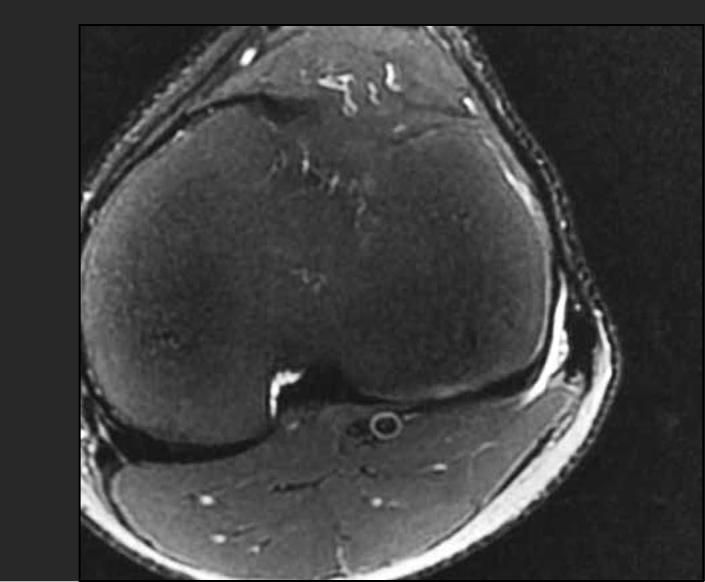

Dislocation of the femoral biceps tendon is rare and is described clinically in the literature as a lateral pain in the knee. It was initially reported as an anomalous insertion of the long head of the femoral biceps. Subsequently, it was found to be caused by abnormal mobility of the tendon over the prominence of the fibular head at certain angles of knee flexion. The objective of the present report was to describe and discuss a condition of lateral knee pain in a swimmer who started to present subluxation of the femoral biceps during sports practice, which incapacitated him from taking part in trials and competitions. The case is discussed in the light of the literature surveyed; the likelihood that the etiology for the trauma leading to this condition was repetition; and the surgical treatment instituted, which led to excellent results and the patient's return to his habitual sports practice.

股二头肌肌腱脱位较为罕见,在文献中临床描述为膝关节外侧疼痛。最初它被报道为股二头肌长头的异常附着。随后发现,它是由肌腱在膝关节屈曲一定角度时在腓骨头突出处的异常活动引起的。本报告的目的是描述和讨论一名游泳运动员膝关节外侧疼痛的情况,该运动员在体育训练中开始出现股二头肌半脱位,这使他无法参加选拔赛和比赛。结合所查阅的文献对该病例进行了讨论;导致这种情况的创伤病因很可能是重复性损伤;以及所采取的手术治疗,该治疗取得了优异的效果,患者恢复了其惯常的体育训练。